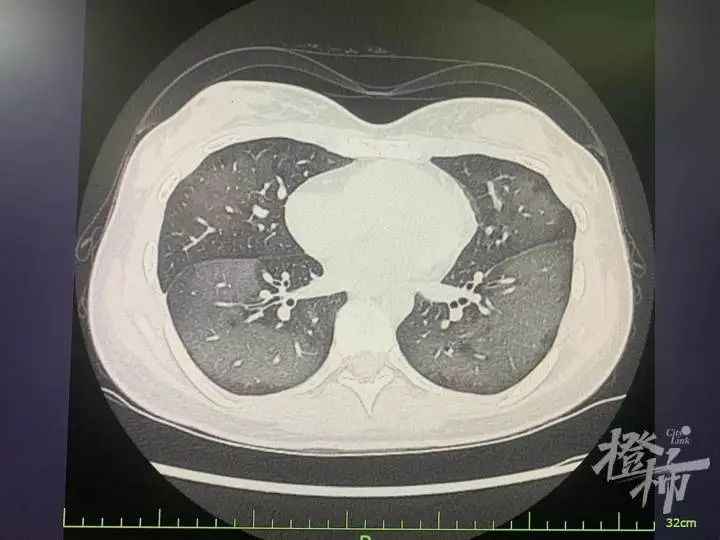

通过CT检查发现

丽丽的双肺呈现

大量白色样病变

报告提醒“白肺”

丽丽被诊断为“急性过敏性肺炎”。急诊专家对丽丽给予吸氧、激素抗炎、抗过敏等对症支持后,急性症状得到缓解,她在呼吸内科病房接受进一步住院治疗。